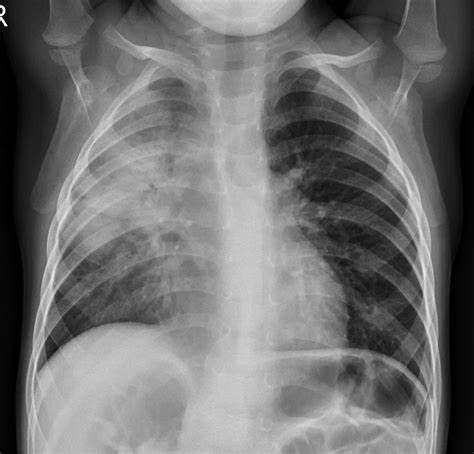

- Chest x-ray

- CT scan